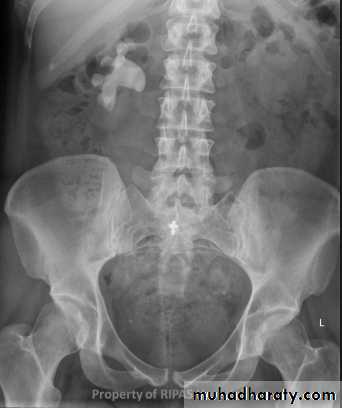

- Over 90% of calculi are radiopaque on plain films and virtually all on CT as very sensitive for detection of calculi, even those that appear radiolucent on plain film.- Most of these stones are a mixture of calcium oxalate and phosphate.

- Only pure uric acid and xanthine stones are radiolucent on plain x-ray but CAN be identified by CT or US , uric acid stones are associated with increased uric acid excretion in urine as in gout.

l.V.U. findings:

-Plain film may be useful in demonstrating calculi. -After contrast injection: Acutely obstructed kidney shows a dense nephrogram (dense opacification of the renal parenchyma).

excretion of contrast (opacification of the collecting system which may take many hours) ,

then the level and degree of obstruction can be determined as dilated pelvi-caliceal system and ureter are followed down to the point of obstruction (point of hold up).

Ddx of stone on KUB :

1. Gall stone2. Calcified LN , cartilage ,fibroid,

3. Phlebolith: round, lucent centre.